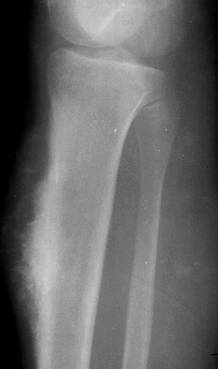

a)   Fibromul – apare ca o zona transparenta metafizara, excentrica, ovalara, conturul intern fiind marginit de o zona sclerozata. Corticala este subtiata, uneori disparuta. Rareori se poate observa o slaba reactie periostala. Afecteaza cu predilectie varsta adulta.

Fig. 83 – Fibrom tibial